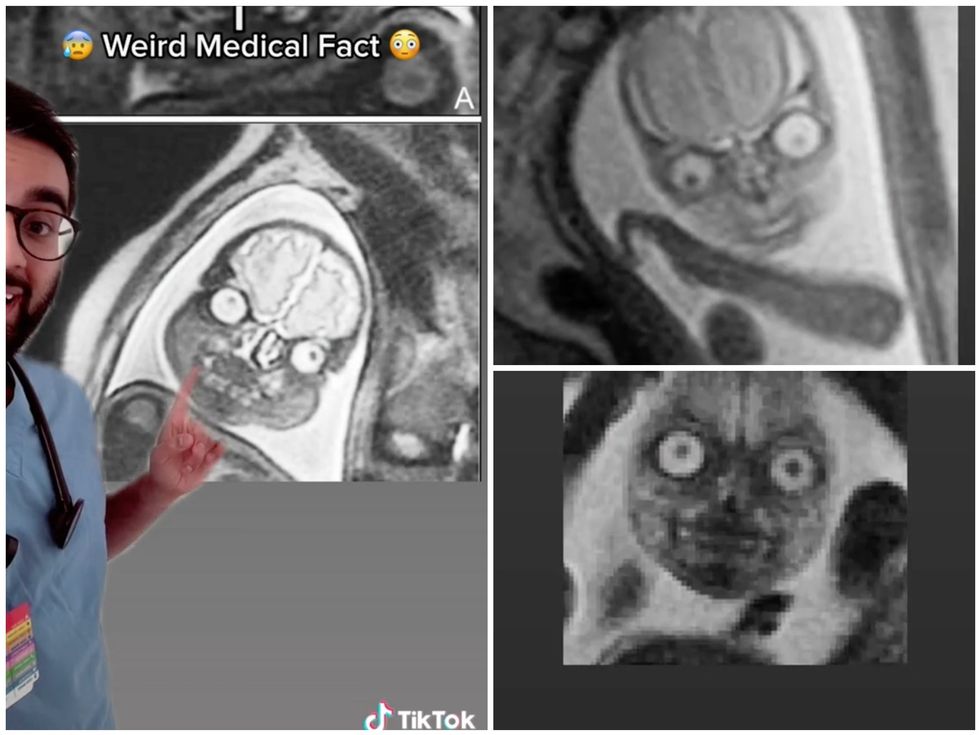

We all know unborn babies are beautiful little miracles, but they don’t necessarily look that way if you put them under an MRI scan.

That’s what one medical student revealed when he showed TikTok users snapshots of what he described as the “the creepiest and funniest thing I’ve seen in medicine.”

The doctor, who goes by the username MadMedicine, said that he and his colleagues don’t tend to show expecting mothers MRI images for fear of terrifying them.

“I don’t think any expecting mothers would want to see this,” he laughed. “First of all I don’t know how I would explain this [...] like, ‘hey, this is the thing growing inside of you’.”

Unveiling the snapshots, the medic described one of them as “straight out of a nightmare”, while in a follow-up video he accepted fellow TikTokers’ suggestions that it bore an uncanny resemblance to… Mr Bean.

The original clip and follow-up vids have now racked up more than 2 million views, with users describing the pictures as demonic or straight out of a horror movie.

“Was I the only one that thought the second one looked a little like Homer Simpson?” a third asked.

Meanwhile, others likened the baby heads to the characters in Tim Burton’s 1996 film Mars Attacks! or the murderous doll in the Chucky films, or just a “cursed jelly baby”.